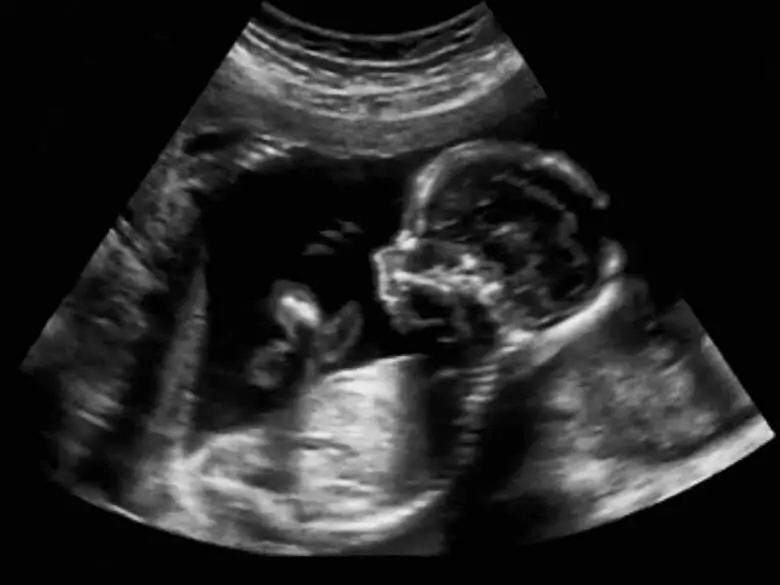

Prenatal tests have long played an important role in gynaecology and obstetrics, but nowadays their value is constantly increasing due to the fact that more and more women are becoming pregnant late. Among prenatal tests, a distinction is made between invasive and completely non-invasive tests - which exact tests are performed in prenatal diagnosis and when are each of these used?